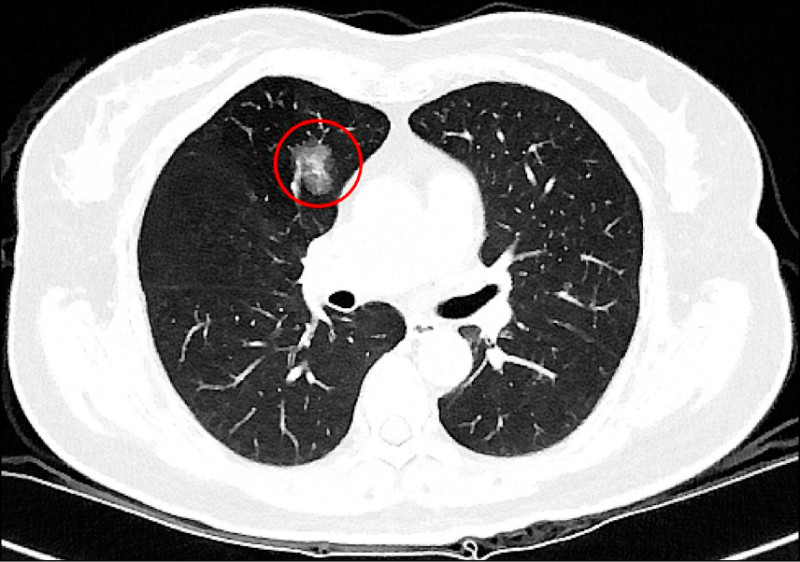

隨著低劑量電腦斷層(LDCT)篩檢日益普及,越來越多民眾在健康檢查或就醫過程中發現肺部小結節,也讓「到底要不要立刻開刀」成為門診中常見疑問,台北慈濟醫院胸腔內科醫師吳智偉針對院內LDCT共6997名篩檢個案進行回溯性分析,結果發現手術切除的病灶中,有約3分之2被證實是惡性腫瘤,另外3分之1為良性腫瘤,由此可知小型肺部結節在影像判讀與切片診斷上極具挑戰。

吳智偉指出,肺癌發生率已居全國第一,影響因子包括抽菸、肺癌家族史及空氣污染等,但臨床上超過一半肺癌患者其實不抽菸,因此即使沒有抽菸習慣,也不能完全輕忽風險,近年政府積極推動低劑量電腦斷層篩檢,提升肺癌早期發現及治療的機會,針對肺部小結節,臨床上雖會依據大小、影像型態、生長狀況以及病人的臨床背景進行綜合判斷,但部分良性病灶在影像上與早期肺癌相似,有些早期惡性病灶則生長緩慢、不易立即判別。

吳智偉說明,以許女士為例,沒有抽菸習慣,也沒有肺癌家族史,卻在64歲健康檢查時,從LDCT檢查中發現1.2公分的肺部結節,之後持續在胸腔內科門診追蹤,7年後,許女士71歲時,結節增大至1.4公分,因為擔憂,她與醫師討論後轉至胸腔外科手術,病理結果確診為第一期肺腺癌,由於屬早期肺癌,術後不需化療,追蹤至今恢復良好,無併發症。

吳智偉說明,許多肺部結節通常需要追蹤很長的時間,才會有些微變化(1年約長大0.1cm),臨床上會根據變化的型態進一步評斷處置方式,極早期的結節因為太小,無法經由穿刺切片確認屬性,他提醒,發現肺結節不必過度恐慌,也不代表一定要立刻動刀,目前國內外的共識是以大小0.8公分作為最基礎的判斷準則,在困難判讀的情況下,建議須定期追蹤,若在追蹤期間出現變大或影像特徵改變,建議與醫師討論或進一步評估手術時機,通常會有機會在零期或第一期及早治療。